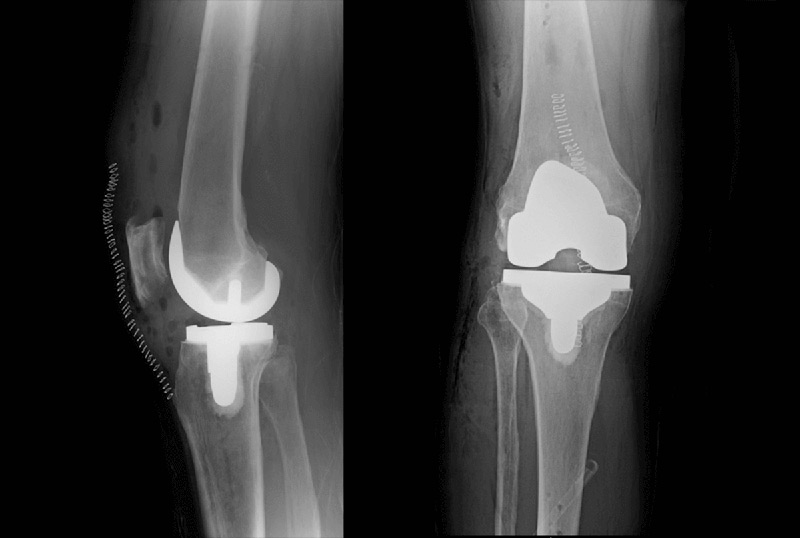

Η τεχνική MAKOplasty αποτελεί την μόνη ρομποτική τεχνική για την πραγματοποίηση τόσο μερικής  αρθροπλαστικής του γόνατος (PKR-MAKOplasty) όσο και ολικής αρθροπλαστικής του γόνατος (TKR-MAKOplasty)

Στην ρομποτικά υποβοηθούμενη αρθροπλαστική (MAKOplasty) όλα ξεκινάνε προεγχειρητικά με μια πολύ υψηλής ανάλυσης αξονική τομογραφία (CT) με την οποία γίνεται η ακριβής αποτύπωση της ανατομίας του γόνατος του κάθε ατόμου σε ένα τρισδιάστατο (3D) μοντέλο.

Αυτό το μοναδικό για τον κάθε ασθενή μοντέλο χρησιμοποιείται στη συνέχεια, αφενός για την δημιουργία ενός στερεοτακτικού παραθύρου (απαραίτητο για την ακριβή αφαίρεση του παθολογικού οστού), αφετέρου για την επιλογή του ιδανικού μεγέθους του εμφυτεύματος και την τοποθέτησή του με τέτοιο τρόπο ώστε να επιτευχτεί η επιθυμητή μετεγχειρητική κάλυψη των οστών και η σωστή ευθυγράμμιση του σκέλους.